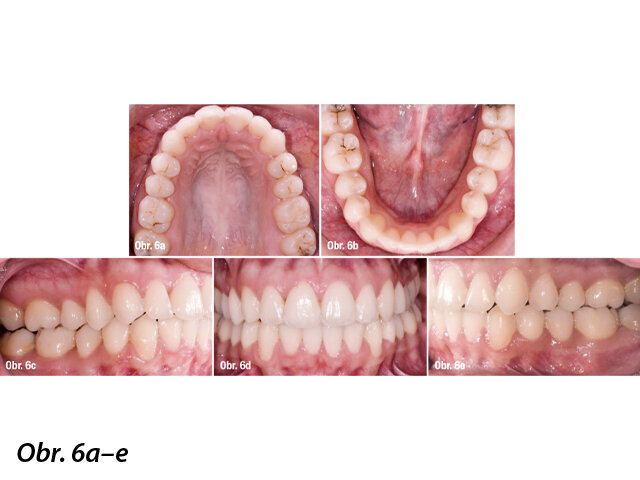

Po jedenácti měsících a celkem 66 alignerech na horní i dolní čelisti byla léčba pacientky dokončena. Všechny cíle léčby se podařilo splnit. Bilaterální vztah I. třídy byl dosažen, oblouky jsou symetrické a vyřešilo se i stěsnání zubů (obr. 6). Podle širokoúhlého rentgenového snímku (obr. 7) byly kořeny paralelně a nebyly zde žádné projevy resorpce kořenů (zcela potvrdit by to ale bylo možné pouze pomocí periapikálního rentgenu). Kefalometrická analýza ukázala, že si horní i dolní řezáky zachovaly svou pozici (původně byly dolní řezáky k linii APog 14 mm, finální poloha řezáků k linii APog byla 13 mm) (obr. 8).